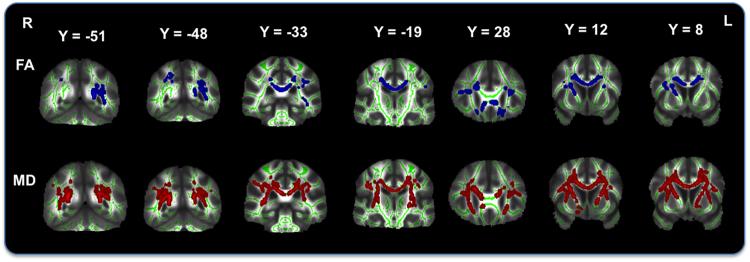

The allostatic load index quantifies the cumulative multisystem physiological response to chronic everyday stress, and includes cardiovascular, metabolic and inflammatory measures. Despite its central role in the stress response, research of the effect of allostatic load on the ageing brain has been limited. We investigated the relation of mid-life allostatic load index and multifactorial predictors of stroke (Framingham stroke risk) and diabetes (metabolic syndrome) with voxelwise structural grey and white matter brain integrity measures in the ageing Whitehall II cohort (N = 349, mean age = 69.6 (SD 5.2) years, N (male) = 281 (80.5%), mean follow-up before scan = 21.4 (SD 0.82) years). Higher levels of all three markers were significantly associated with lower grey matter density. Only higher Framingham stroke risk was significantly associated with lower white matter integrity (low fractional anisotropy and high mean diffusivity). Our findings provide some empirical support for the concept of allostatic load, linking the effect of everyday stress on the body with features of the ageing human brain.

应激多系统负荷指数定量评估了慢性日常压力对多系统生理反应的累积效应,其中包括心血管、代谢和炎症指标。尽管应激反应的中心角色,但是对于应激多系统负荷指数对衰老大脑的影响的研究一直很有限。我们在 Whitehall II 队列(N=349,平均年龄 69.6(SD 5.2)岁,N(男性)=281(80.5%),扫描前平均随访时间 21.4(SD 0.82)年)中,研究了中年应激多系统负荷指数以及中风(Framingham 中风风险)和糖尿病(代谢综合征)的多因素预测因素与脑灰质和白质结构完整性的体素水平测量之间的关系。三种标志物水平越高,与灰质密度越低显著相关。只有Framingham 中风风险较高与白质完整性降低(低各向异性分数和高平均弥散度)显著相关。我们的研究结果为应激多系统负荷概念提供了一些经验支持,将日常压力对身体的影响与人类衰老大脑的特征联系起来。